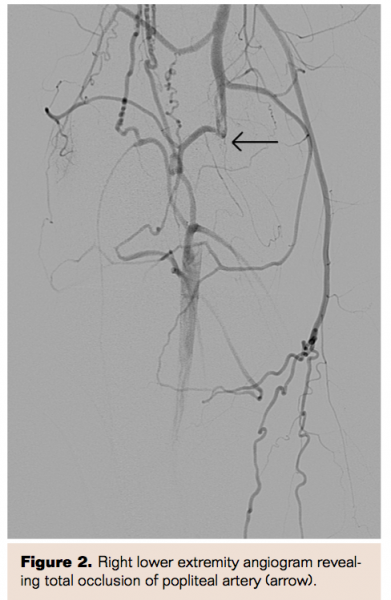

A 17-year-old white male who is the sibling of the patient described in case 1 was referred to vascular surgery 1 year after presentation of his sibling with worsening right lower extremity disabling claudication for the past 6 months. The patient did not have any significant previous medical or surgical history. Upon physical examination, the patient was found to have no pedal or popliteal pulses in his right lower extremity. The patient underwent angiography, which revealed complete occlusion of the right popliteal artery (Figure 2). Using a posterior popliteal approach to expose the right popliteal fossa, the popliteal artery was found to be medially displaced by the medial head of the gastrocnemius muscle. An interposition lesser saphenous vein graft was used to restore blood flow. The patient had an uneventful postoperative course and was discharged home on postoperative day 1. In outpatient follow-up the patient had palpable pedal pulses with complete recovery.